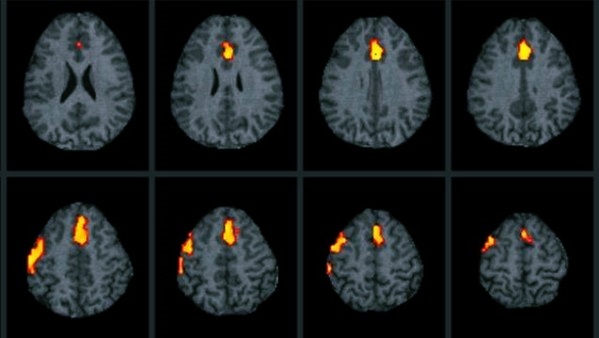

Для нейронов крайне губительно кислородное голодание, даже если оно не длительное. Буквально после нескольких минут полного отсутствия подачи кислорода ткани начинают гибнуть. Электроэнцефалограмма в этом случае покажет нулевую линию. Это означает, что мозговая активность отсутствует полностью.

При энцефалографии исследуется деятельность мозга. При этом аппарат регистрирует биотоки, их работа воспроизводится на бумаге в форме кривых.

Смерть головного мозга определяется отсутствием всех признаков мозговой активности, включая отсутствие реакции на свет, отсутствие дыхательных движений и отсутствие реакции на болевые стимулы. Также важно отметить, что необходимо провести специальные тесты, такие как электроэнцефалография, для подтверждения отсутствия электрической активности в мозге.

Используйте медицинские технологии для диагностики. Современные методы, такие как электроэнцефалография (ЭЭГ) или компьютерная томография (КТ), могут помочь в определении состояния мозга и подтверждении его смерти.